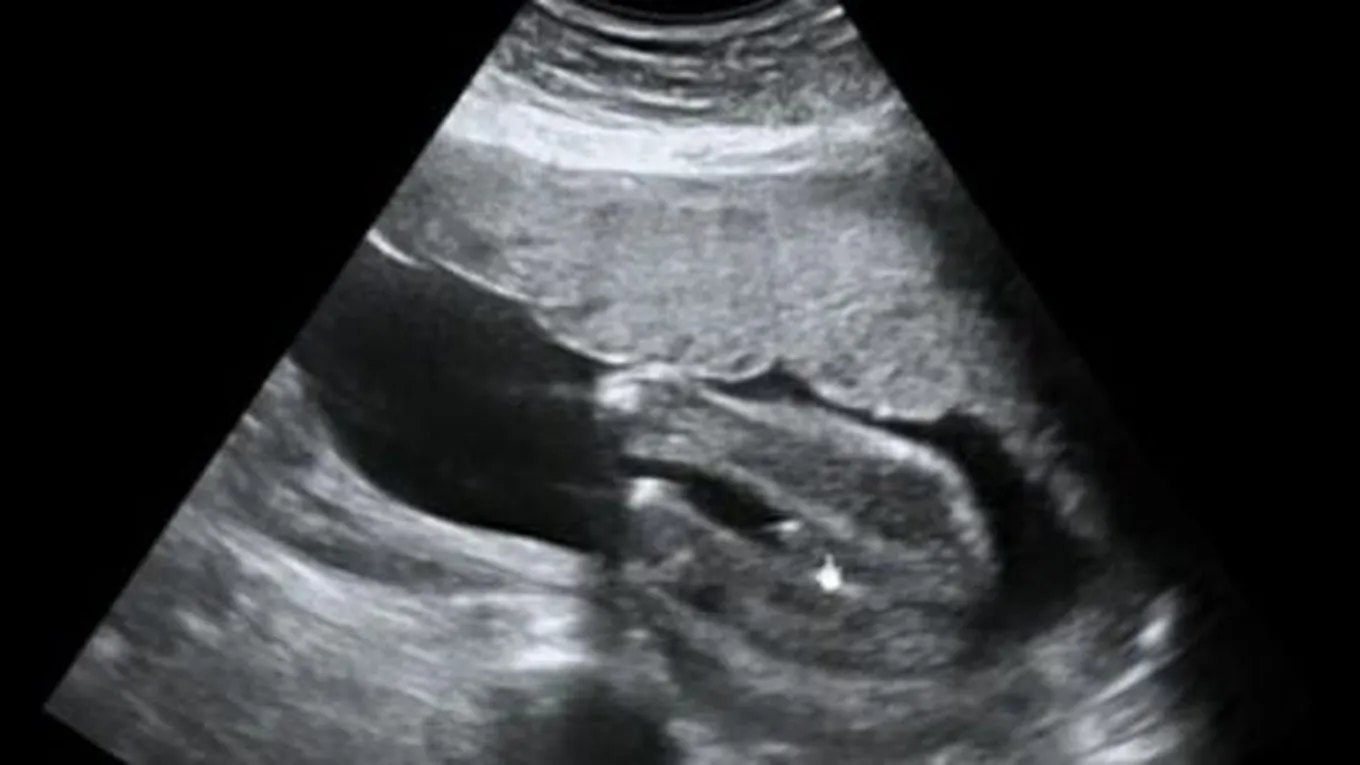

منذ لحظة إخصاب البويضة بالحيوان المنويّ يتحدّد نوع أو جنس الجنين، بالإضافة إلى جميع الصفات الجينيّة والوراثيّة الأخرى له، كما تبدأ الأعضاء التناسليّة بالتشكّل منذ الأسبوع السادس من الحمل، وعلى الرغم من ذلك فإنّ الطبيب قد لا يكون قادراً على معرفة نوع الجنين حتى الوصول إلى منتصف الحمل تقريباً، ويمكن التعرّف على نوع الجنين في بعض الحالات منذ الأسبوع السادس عشر من الحمل، أو قد يحتاج الطبيب إلى عدّة أسابيع أخرى بناءً على موقع الجنين في الرحم، ولكن في معظم الحالات يكون الطبيب قادراً على الكشف عن نوع الجنين بحلول الأسبوع الثامن عشر من الحمل تقريباً،[2][3] وتعتمد دقّة تحديد نوع الجنين على العديد من العوامل المختلفة، مثل نوع الجهاز المستخدم، وعُمُر الجنين، وتجدر الإشارة إلى وجود عدد من العلامات التي يعتمد عليها الطبيب في الكشف عن نوع الجنين، نذكر منها الآتي:[4]

- الإناث: تعتقد بعض الأمهات أنّ غياب ظهور القضيب في صورة السونار يعني أنّ الجنين أنثى، وفي الحقيقة لا يمكن الاعتماد على هذه النظريّة، لأنّ كلا الأعضاء الجنسيّة للجنين الذكر والأنثى قد تبدو متشابهة خصوصاً خلال مراحل الحمل المبكّرة، ويتمكّن الطبيب من تحديد نوع الجنين كأنثى في حال القدرة على الكشف عن وجود الشفران والبظر في منطقة الأعضاء التناسليّة.

- الذكور: يمكن تحديد الحمل بجنين ذكر من خلال قدرة الطبيب على الكشف عن بروز في مقدّمة القضيب لدى الجنين من خلف الخصيتين، وقد يصعب رؤية القضيب في العديد من الحالات اعتماداً على العوامل التي تمّ ذكرها سابقاً.